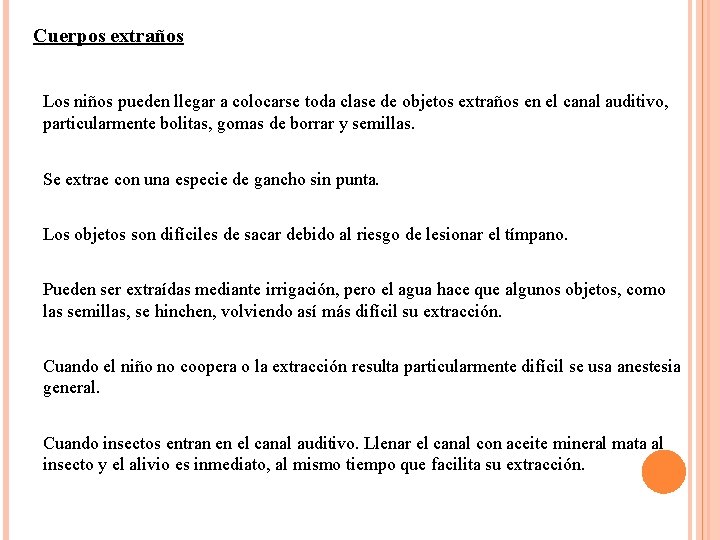

Cuerpos extraños Los niños pueden llegar a colocarse toda clase de objetos extraños en el canal auditivo, particularmente bolitas, gomas de borrar y semillas. Se extrae con una especie de gancho sin punta. Los objetos son difíciles de sacar debido al riesgo de lesionar el tímpano. Pueden ser extraídas mediante irrigación, pero el agua hace que algunos objetos, como las semillas, se hinchen, volviendo así más difícil su extracción. Cuando el niño no coopera o la extracción resulta particularmente difícil se usa anestesia general. Cuando insectos entran en el canal auditivo. Llenar el canal con aceite mineral mata al insecto y el alivio es inmediato, al mismo tiempo que facilita su extracción.